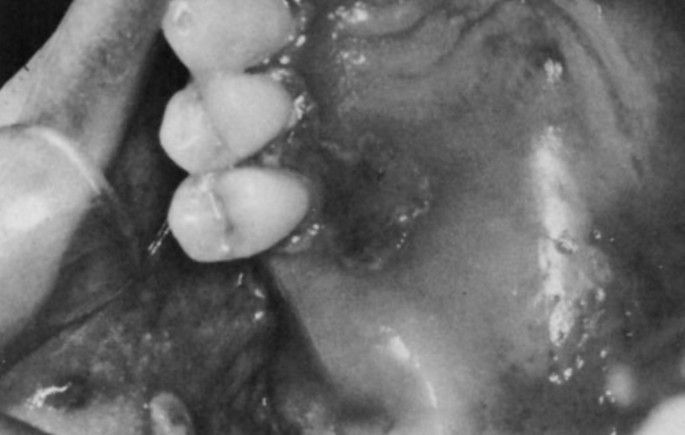

Chronic herpes simplex infection of the palate in a patient taking chemotherapy for acute leukemia.